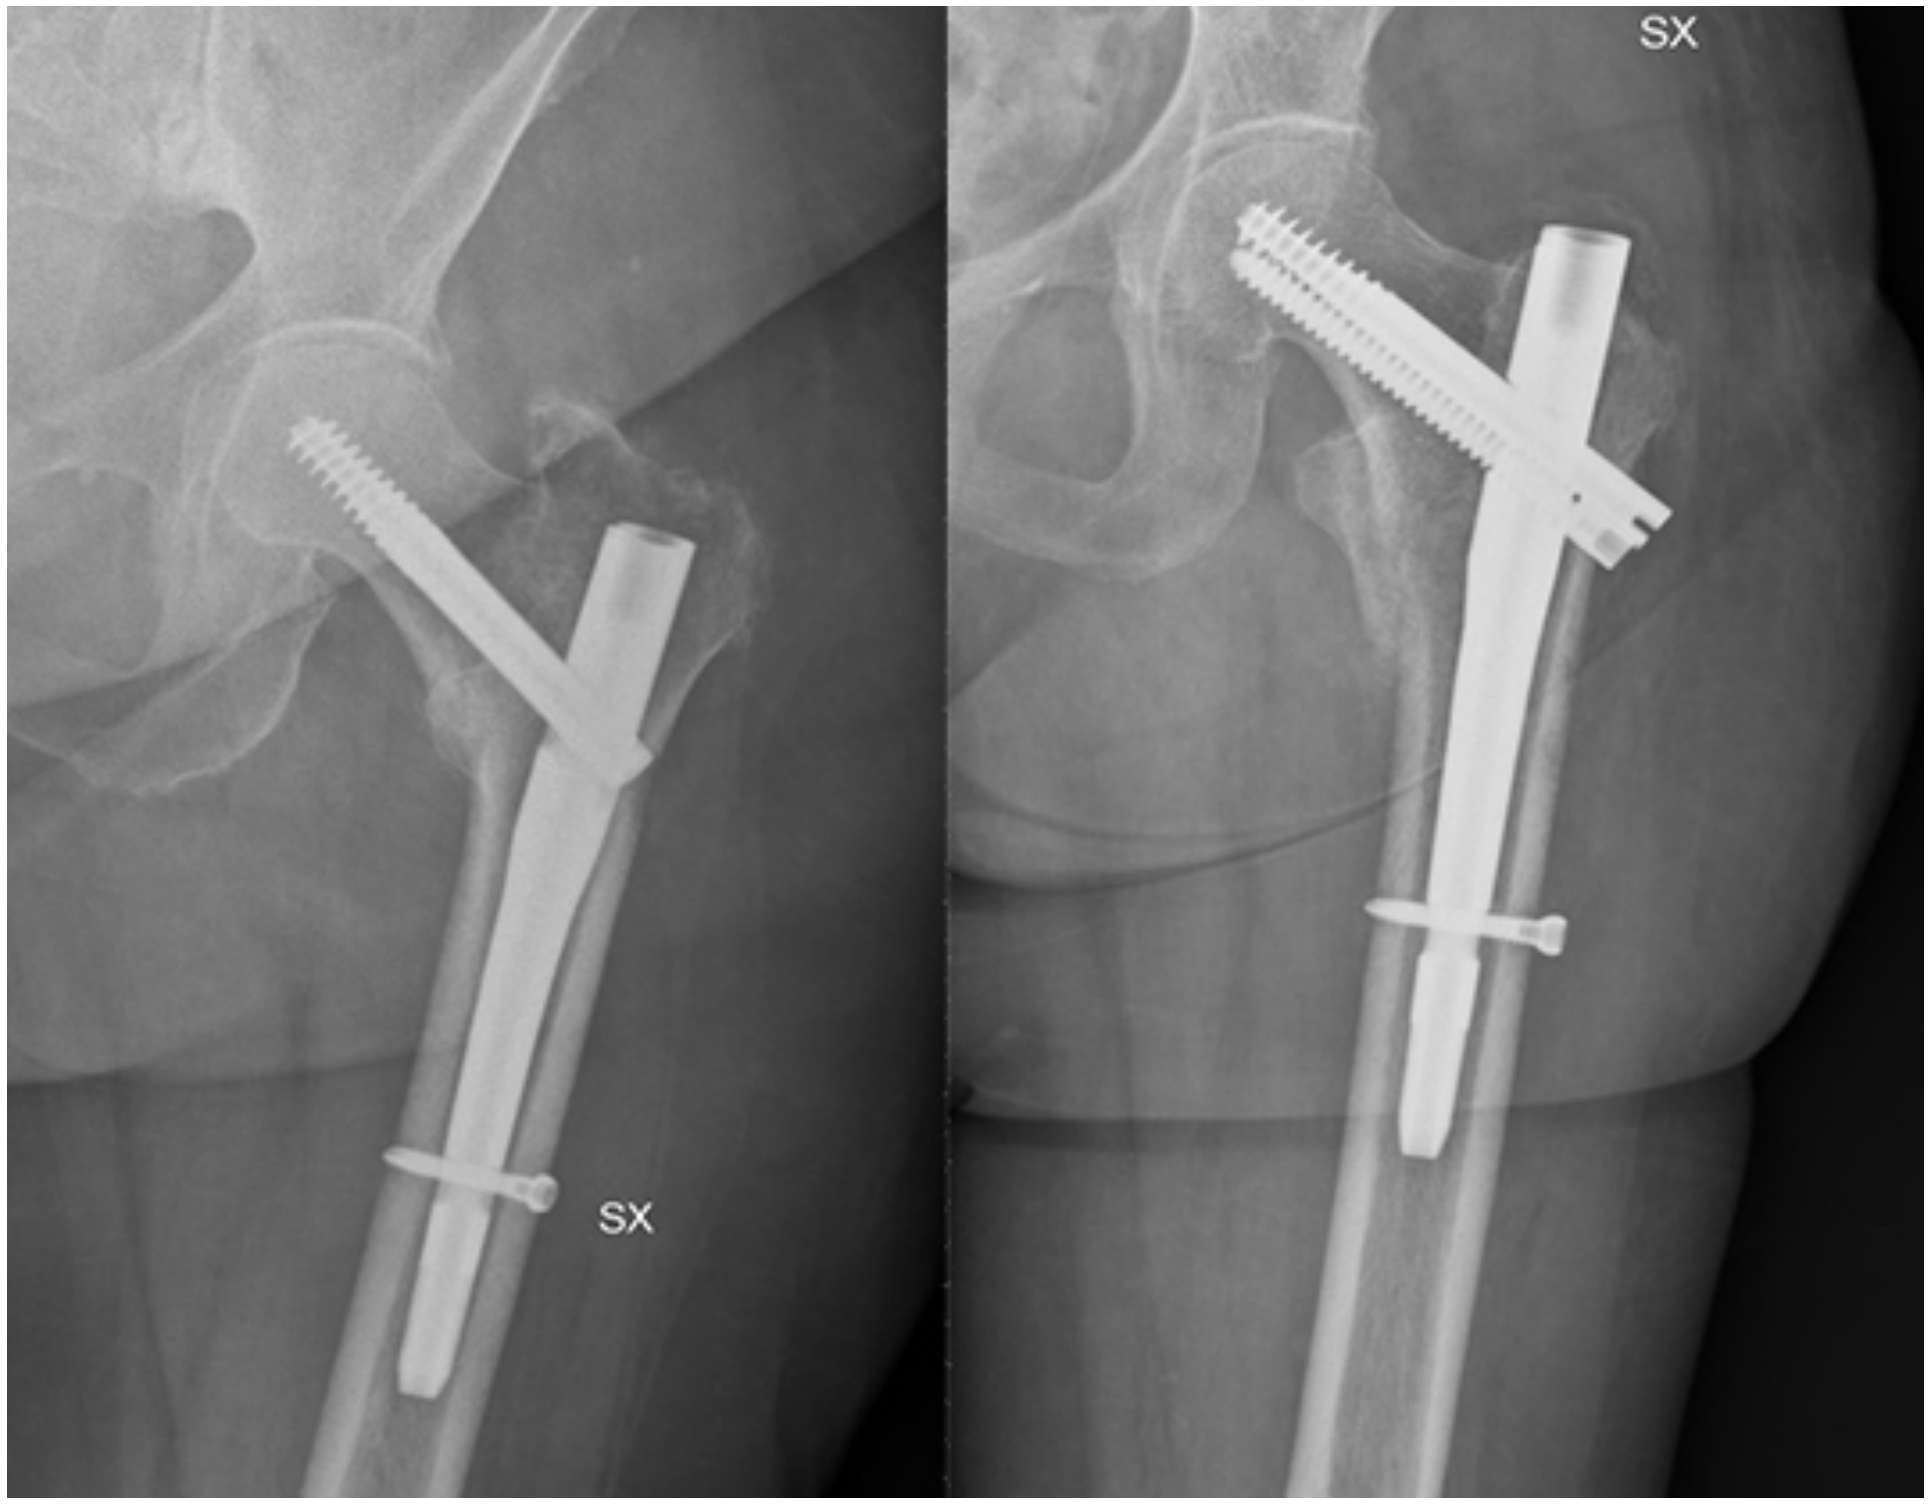

- Cipollaro, L.; Aicale, R.; Maccauro, G.; Maffulli, N. Single- versus double-integrated screws in intramedullary nailing systems for surgical management of extracapsular hip fractures in the elderly: A systematic review. J. Biol. Regul. Homeost. Agents 2019, 33, 175–182. [Google Scholar] [PubMed]

- Queally, J.M.; Harris, E.; Handoll, H.H.G.; Parker, M.J. Intramedullary nails for extracapsular hip fractures in adults. Cochrane Database Syst. Rev. 2014, 12, CD004961. [Google Scholar] [CrossRef] [PubMed]

- Parker, M.J.; Handoll, H.H. Gamma and other cephalocondylic intramedullary nails versus extramedullary implants for extracapsular hip fractures in adults. Cochrane Database Syst. Rev. 2010, 8, CD000093. [Google Scholar] [CrossRef]